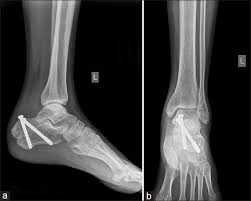

What are the surgical interventions for calcaneal #?